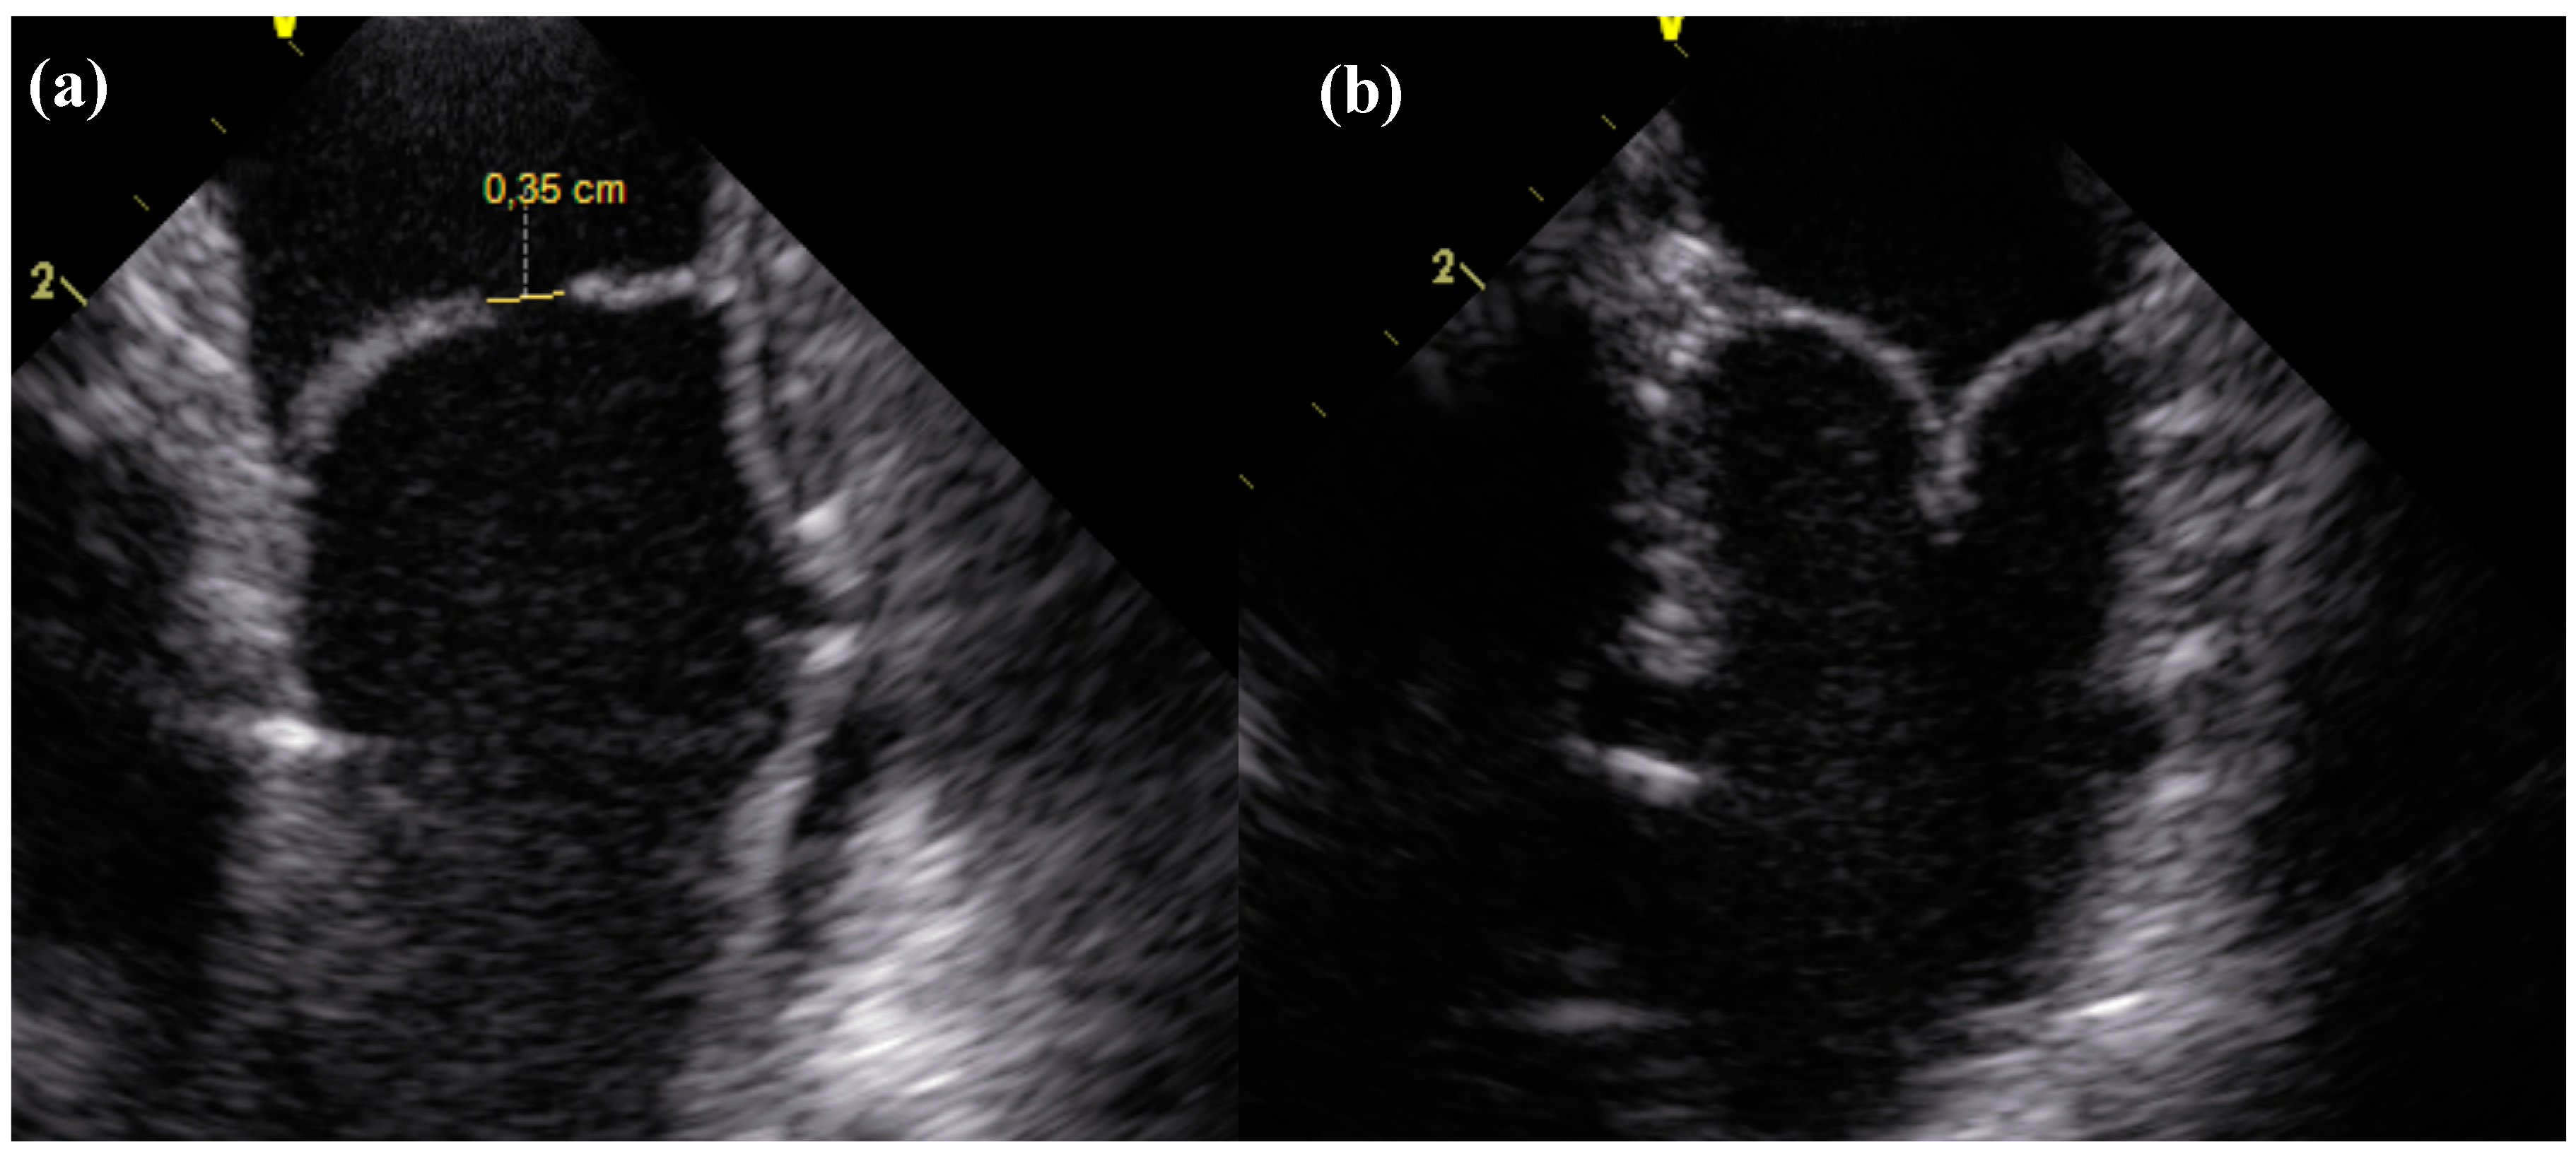

2.1. ICE

Valve functionality directly after implantation as well as after 24 weeks shows substantial improvement from first to second generation dTEHV. Even after 52 weeks, 6 out of 9 second generation dTEHV still remaining in the experiment showed only mild insufficiency (median insufficiency grade: Severe), whereas for the first generation dTEHV 4 out of 5 valves showed severe regurgitation at 24 weeks already (median insufficiency grade: Severe), mainly due to coaptation deficit. (Figure 2 and Figure 3).

Figure 2.

Longitudinal section of the dTEHV during intracardiac echocardioraphy. (a) Coaptation deficit of 0.35 cm 24 weeks after implantation in a first generation dTEHV; (b) Coaptation 24 weeks after implantation in a second generation dTEHV (Coaptation was 0.5 cm).